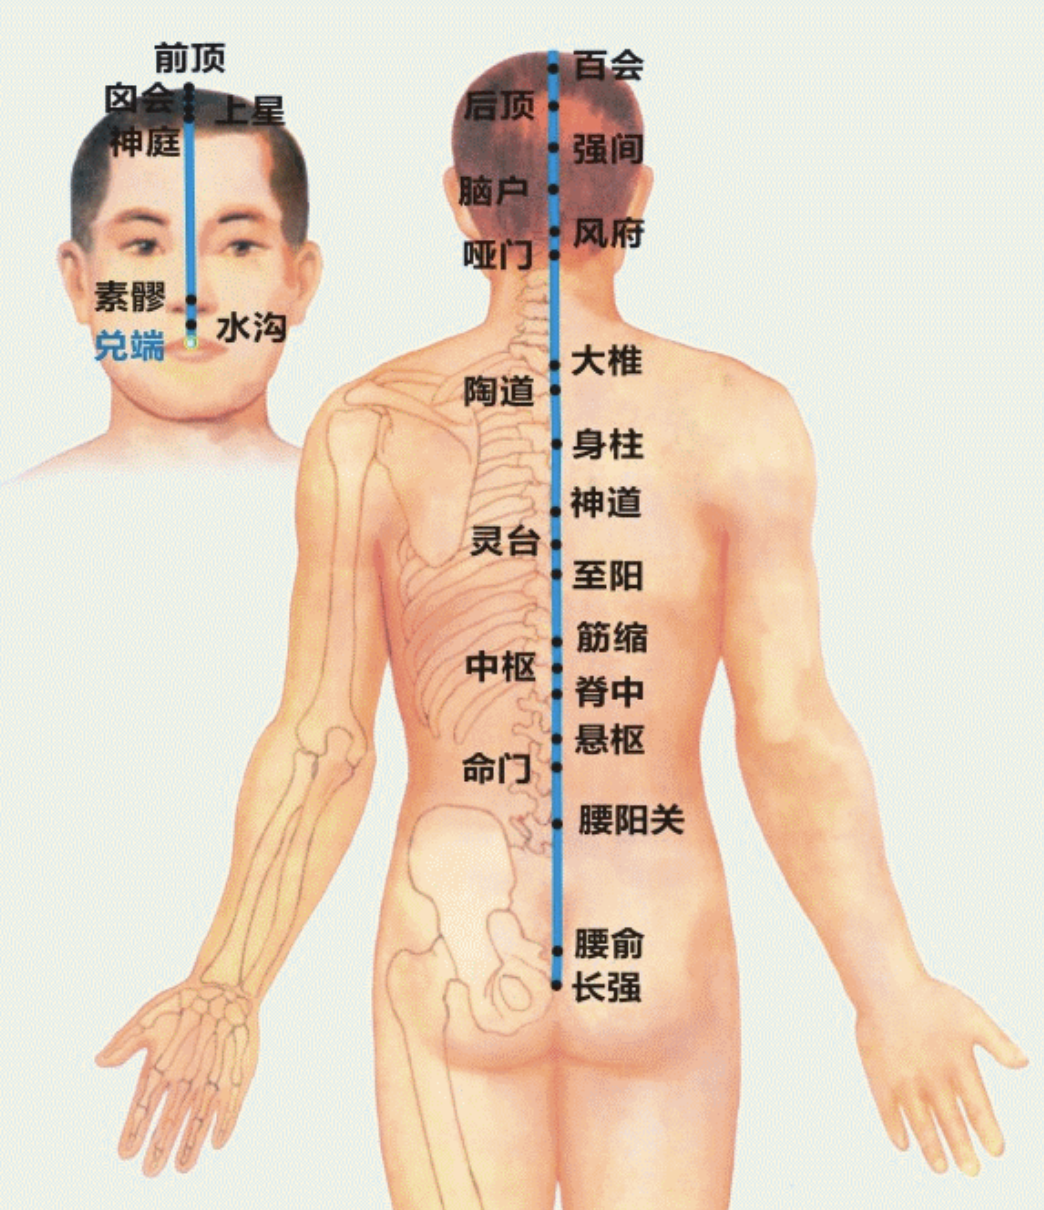

【(十三)督脉(图10-31-1)】

1、经脉循行 起于小腹内,下出于会阴部,向后行于脊柱的内部,上达项后风府,进入脑中,上行巅顶,沿前额下行鼻柱。

2、主要病候 脊柱强痛,角弓反张等证。

3、主治概要 神志疾病,热病,腰骶、背、头项、生殖疾患及循行所过部位相应内脏病证。

4、督脉歌诀 督脉行背之中行,二十八穴始长强。腰俞阳关入命门,悬枢脊中上中枢。筋缩至阳归灵台,神道身柱陶道周。大椎哑门连风府,脑户强间后顶排。百会前顶通囟会,上星神庭素髎对。水沟兑端在唇上,龈交上齿缝之内。